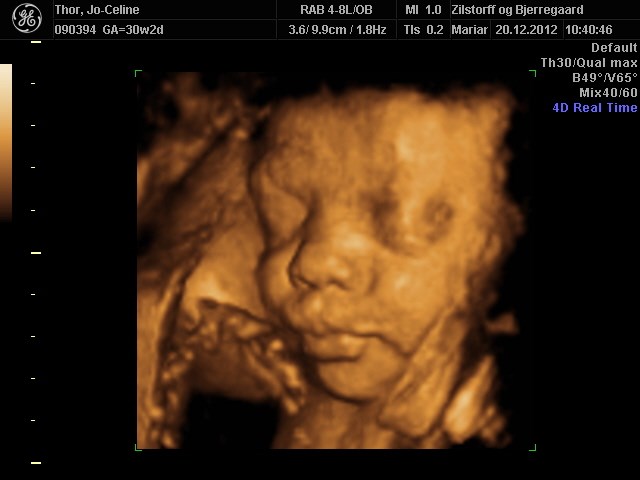

Søger man på Google kommer der kun 3D-billeder.

Så jeg vil høre om nogen herinde har et billede eller to fra uge 28 de vil vise? Og hvor lang var jeres baby, og fik I vægt at vide?